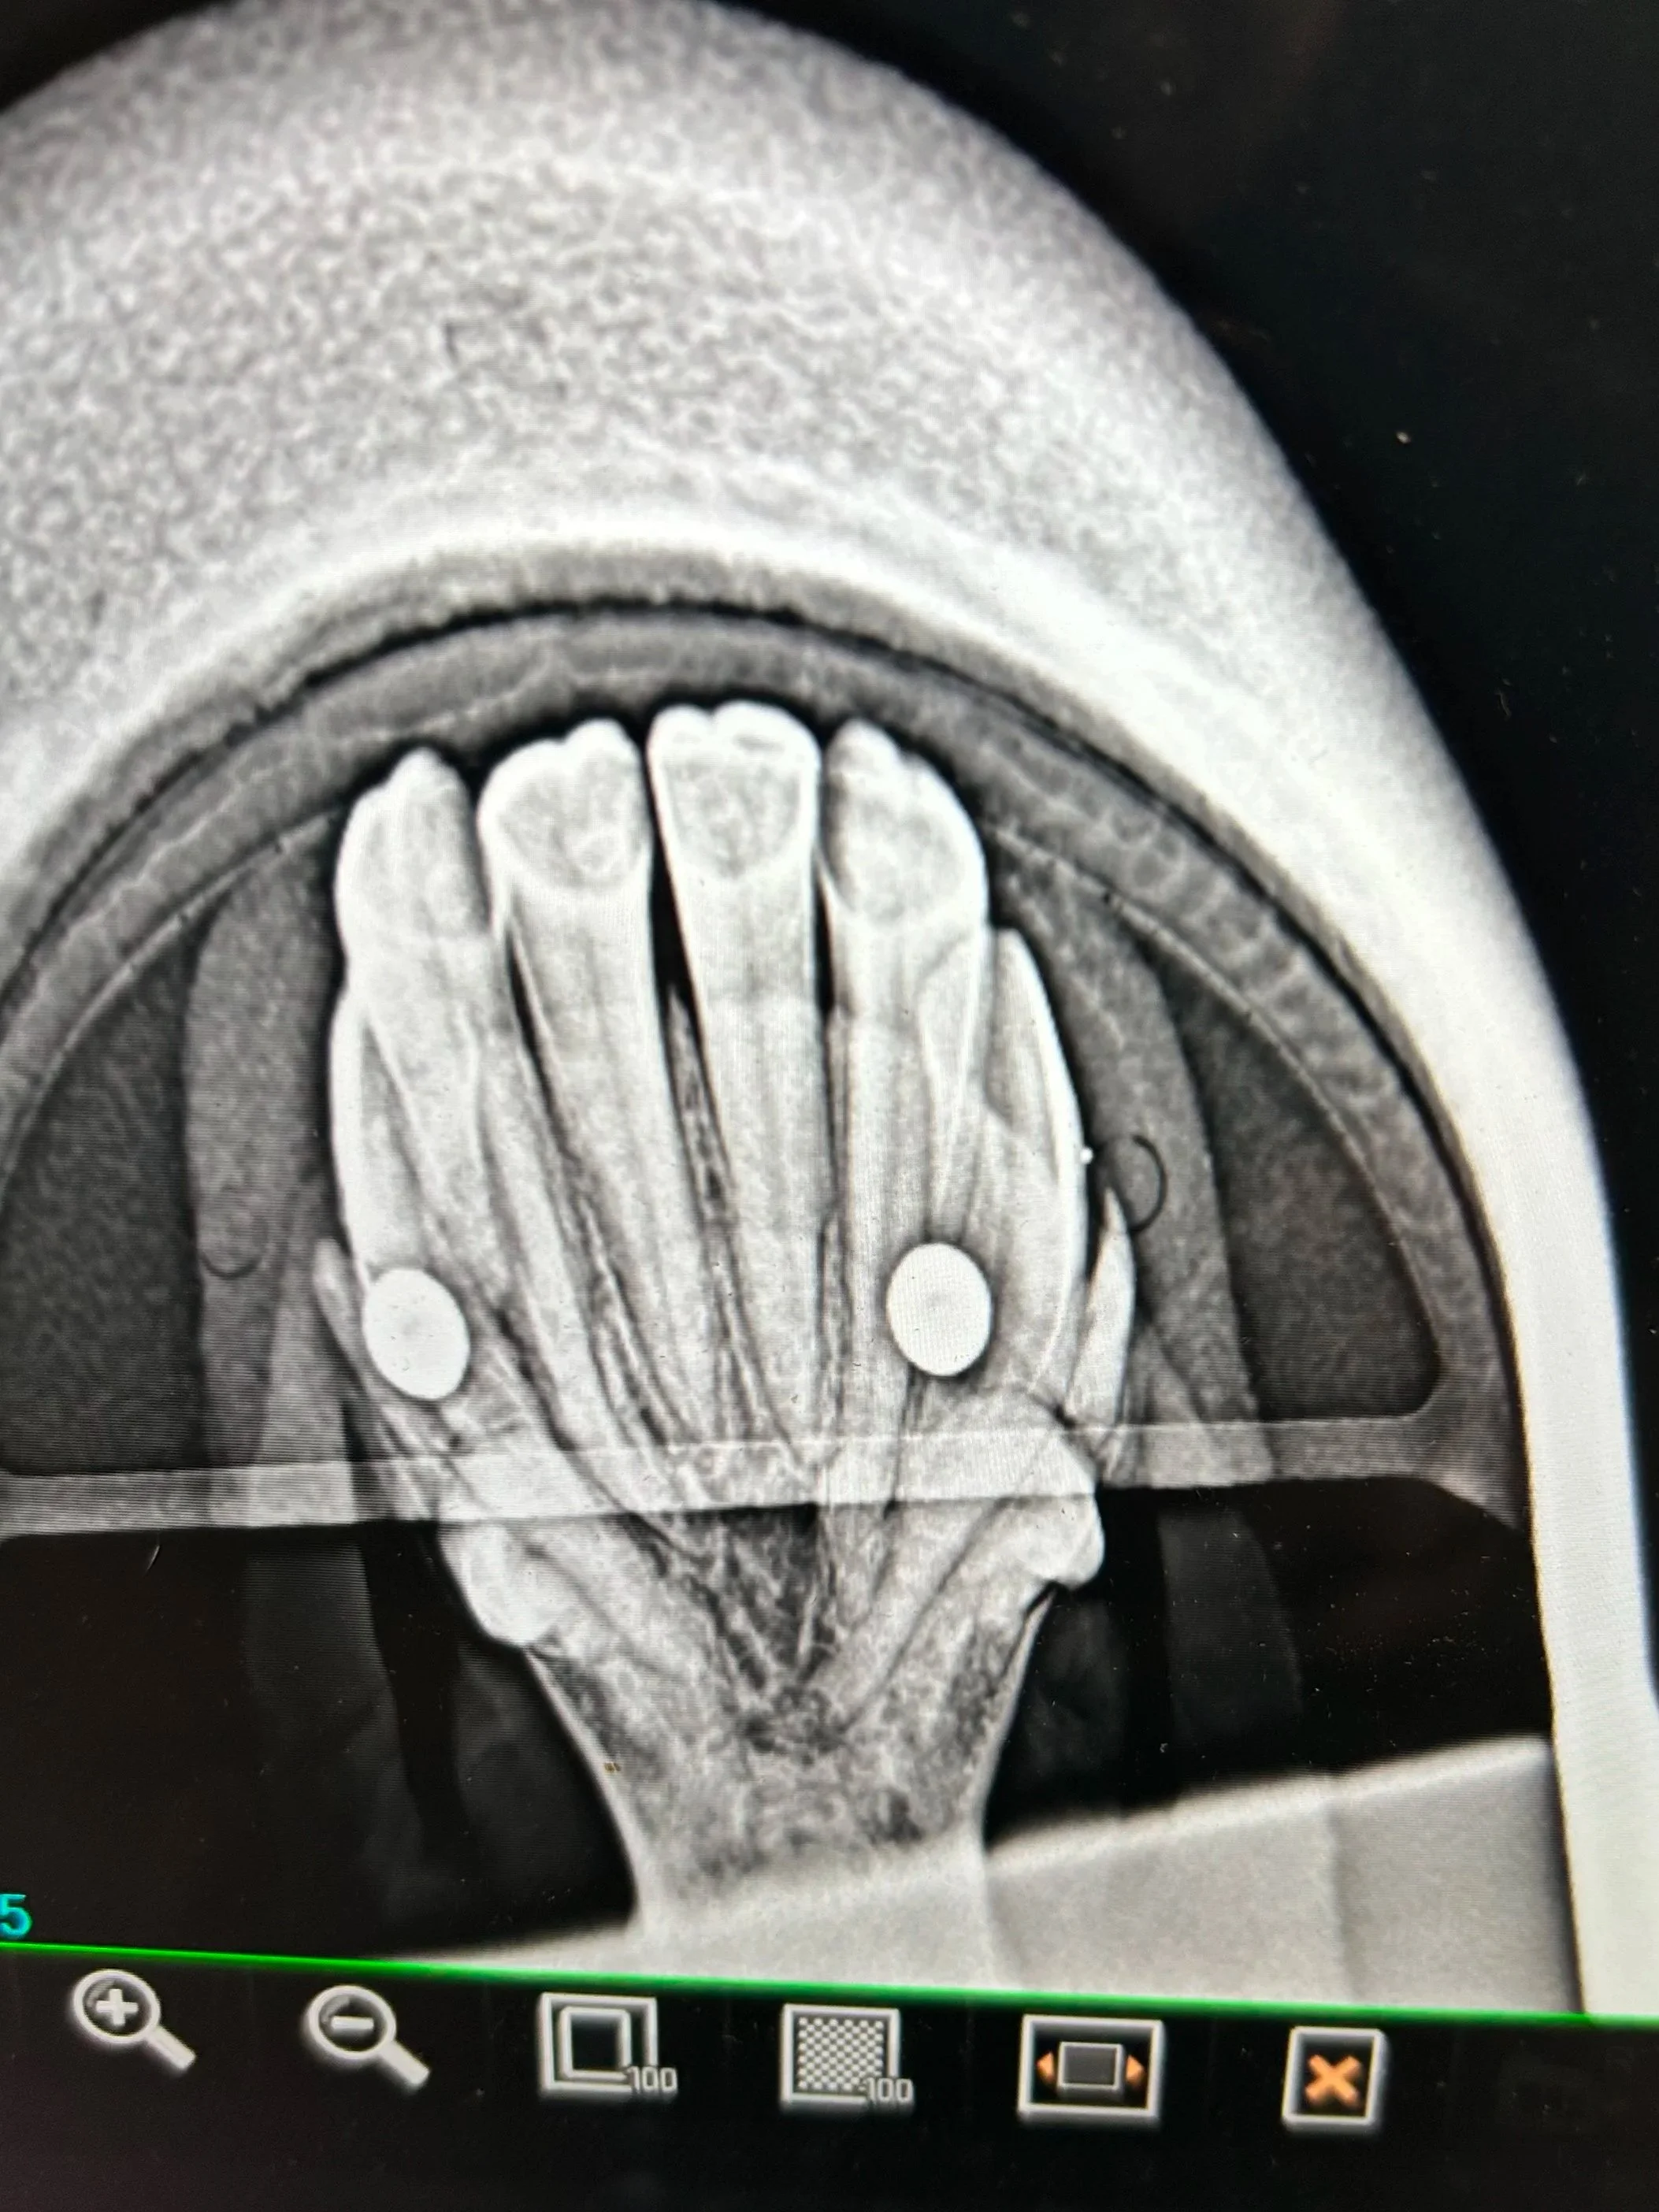

If EOTRH is suspected, a visual exam alone is not enough. The only way to officially diagnose the condition is through radiographs of the incisor teeth. X-rays allow veterinarians to identify characteristic changes, including abnormal tooth root shapes and erosion of the surrounding bone — hallmark indicators of EOTRH.